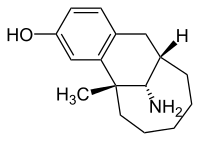

There are a number of broad classes of opioids:[260]

- Natural opiates: alkaloids contained in the resin of the opium poppy, primarily morphine, codeine, and thebaine, but not papaverine and noscapine which have a different mechanism of action

- Esters of morphine opiates: slightly chemically altered but more natural than the semi-synthetics, as most are morphine prodrugs, diacetylmorphine (morphine diacetate; heroin), nicomorphine (morphine dinicotinate), dipropanoylmorphine (morphine dipropionate), desomorphine, acetylpropionylmorphine, dibenzoylmorphine, diacetyldihydromorphine;[261][262]

- Semi-synthetic opioids: created from either the natural opiates or morphine esters, such as hydromorphone, hydrocodone, oxycodone, oxymorphone, ethylmorphine and buprenorphine;

- Fully synthetic opioids: such as fentanyl, pethidine, levorphanol, methadone, tramadol, tapentadol, and dextropropoxyphene;

- Endogenous opioid peptides, produced naturally in the body, such as endorphins, enkephalins, dynorphins, and endomorphins.

- Endogenous opioids, non-peptide: Morphine, and some other opioids, which are produced in small amounts in the body, are included in this category.

- Natural opioids, non-animal, non-opiate: the leaves from Mitragyna speciosa (kratom) contain a few naturally-occurring opioids, active via Mu- and Delta receptors. Salvinorin A, found naturally in the Salvia divinorum plant, is a kappa-opioid receptor agonist.[263]